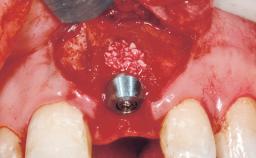

Late Flapless Placement of an Implant in a Maxillary Left Central Incisor Site

A 39-year-old male patient presented with a chief complaint of discomfort and gingival discoloration around his maxillary left central incisor. He was in good general health and was a non-smoker. His past dental history was significant because of the traumatic fracture of tooth 21 in a sporting accident at age 13. Initial dental treatment included endodontic therapy and a full-coverage restoration. The patient became symptomatic 5 years later, when structural failure of the tooth resulted in the dislodgment of the crown. Endodontic retreatment, apical surgery, and post-and-core restoration were performed.

| Bone Volume | Deficient horizontally, requiring prior grafting |

| Esthetic Risk | High |